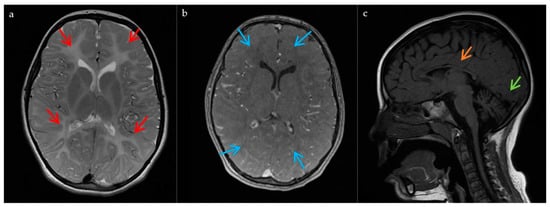

| Patient | Diffuse Hypomyelination | Cerebellar Atrophy | Thin Corpus Callosum |

|---|---|---|---|

| Index | + | + | + |